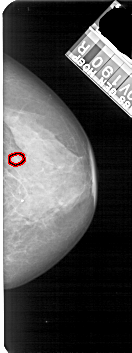

A_1683_1.RIGHT_MLO

RIGHT_MLO LINES 5251 PIXELS_PER_LINE 2386 BITS_PER_PIXEL 12 RESOLUTION 43.5 OVERLAY

FILE: A_1683_1.RIGHT_MLO.OVERLAY

TOTAL_ABNORMALITIES 1

ABNORMALITY 1

LESION_TYPE MASS SHAPE OVAL MARGINS OBSCURED

ASSESSMENT 3

SUBTLETY 3

PATHOLOGY BENIGN

TOTAL_OUTLINES 1

BOUNDARY